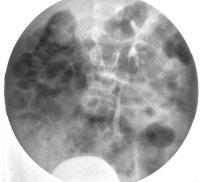

Die Differentialdiagnostik pyelonephritische Zwergniere oder kleine Niere bei Refluxnephropathie erfordert ein Miktionszysturethrogramm. Fernerhin DMSA-Nierenszintigraphie (

s. Bildgebende Verfahren).

Das diagnostische Vorgehen bei dem vesikoureteralen Reflux bzw. der Refluxnephropathie ist in Algorithmen, deren Eingangskriterien variieren, dargestellt (

Abbildung 16). Sie beinhalten aktuelle klinische Symptome, anamnestische Angaben und das Alter der Patienten.Im Vordergrund stehen sonografische Verfahren, die durch die wenig strahlenbelastenden nuklearmedizinischen Methoden ergänzt werden können, ohne dass jedoch in den meisten Fällen auf eine radiologische Miktionszysturethrographie (MCU) verzichtet werden kann.

Folgt man Sigel, so ist das MCU noch immer der Goldstandard (

Abbildung 16)